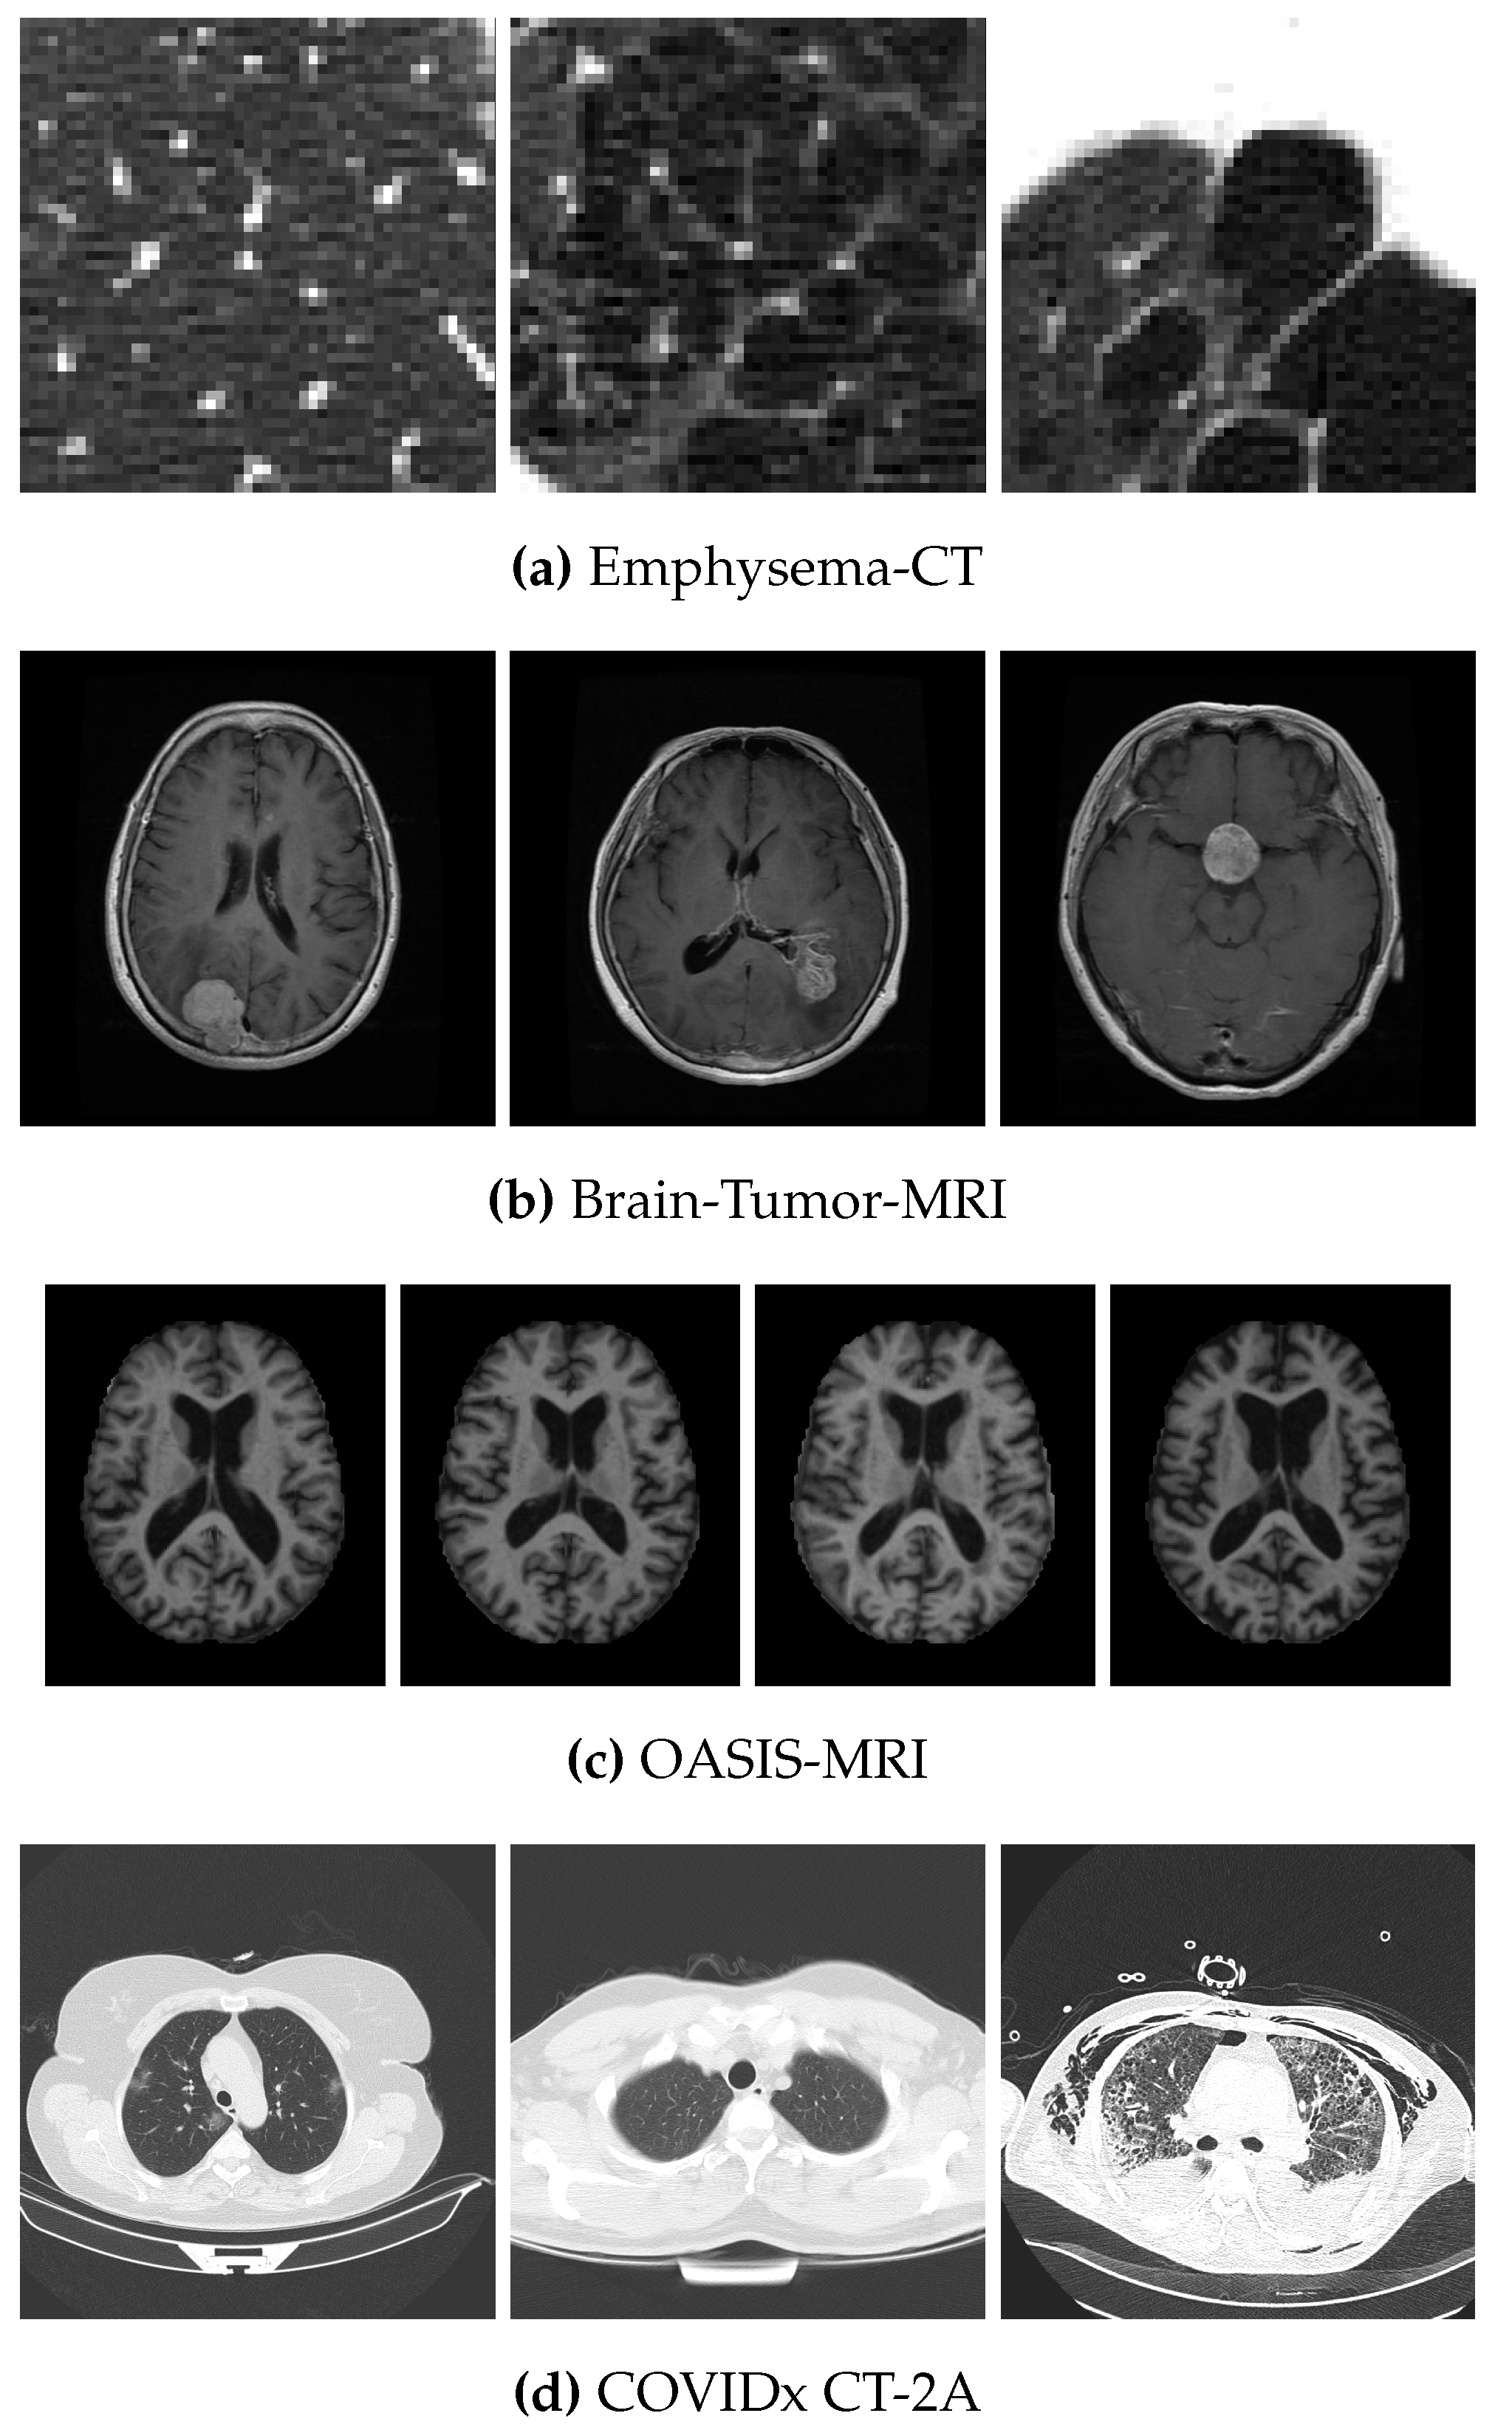

4.1. Data Sets

- Gunraj, H.; Wang, L.; Wong, A. COVIDNet-CT: A Tailored Deep Convolutional Neural Network Design for Detection of COVID-19 Cases From Chest CT Images. Front. Med. 2020, 7, 1025. [Google Scholar] [CrossRef] [PubMed]

| Data Set | No. of Images | Size | Classes | No. of Images per Class |

| COVIDx CT-2A | 4942 | 3 | 3253–873–816 |